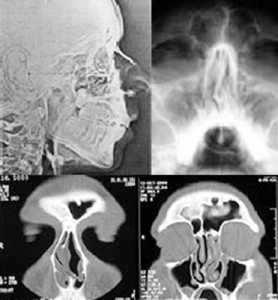

| RÖNTGEN | Nasennebenhöhlen, evtl. seitliche Aufnahme |

| CT | Nasennebenhöhlen-Computertomographie / NNH CT |